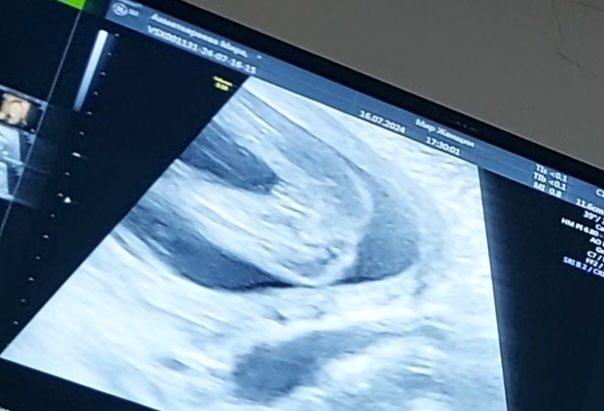

Всем доброго дня! На 18 неделе на плановом УЗИ сказали будет девочка. Сделали фото докозательство😊но многие говорят что на мальчика похож. Может есть среди вас кто хорошо разбирается в таких снимках. А как вы думаете кто там?

Девочка конечно)) ну где тут мальчик то. Вот мое УЗИ с мальчиком )))

Ну тут прям четко пирожок видно же😁 девочка 100%. У мальчиков уже пипка торчит на таких сроках, не спутаешь точно)

100% девочка. У моей на узи в 21 неделю точно такая же складочка между ножками😀 Но у меня еще нипт на 11 неделе указал, что девочку ждем. Так что , сомнений нет.